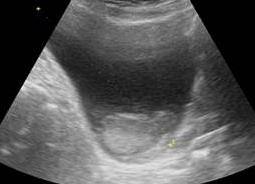

Ультразвуковое исследование (УЗИ) — это наиболее легкий, безболезненный и безопасный метод, дающий необходимую информацию о строении внутренних органов и их функционировании. Этот способ диагностики используют как для обследования взрослых, так и детей, так как он не имеет противопоказаний. Подробнее ...